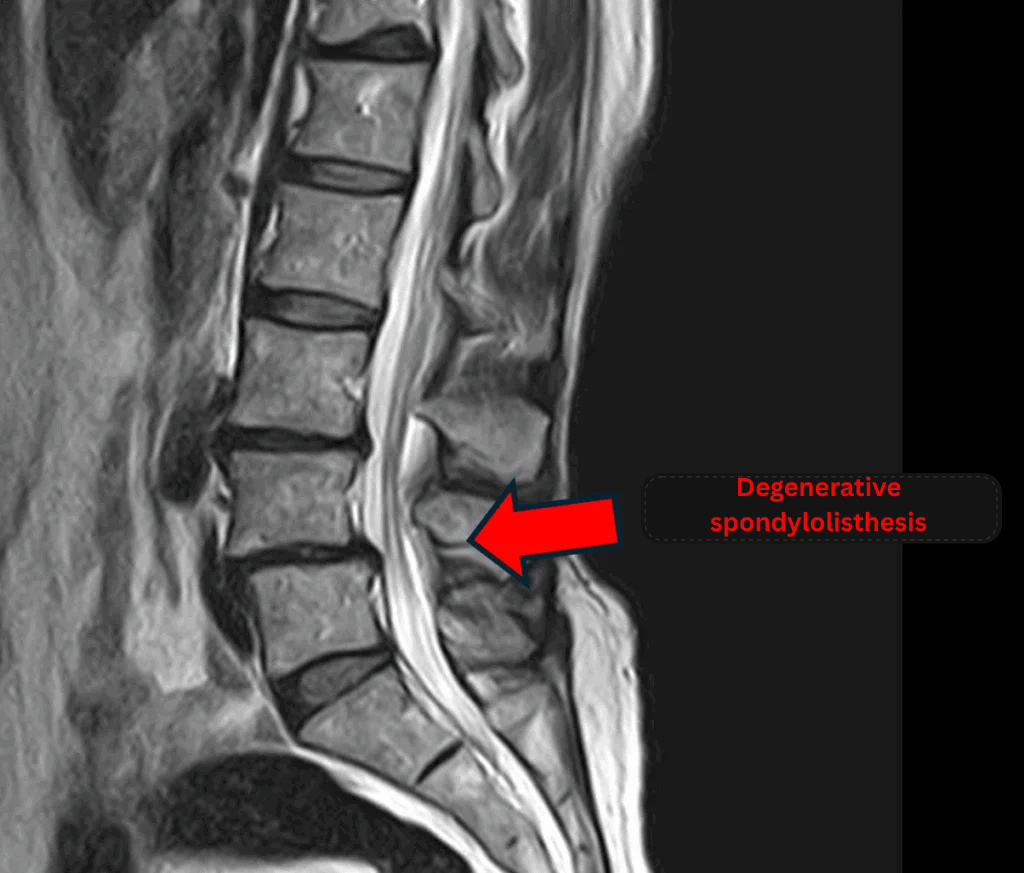

Diagnosed with degenerative spondylolisthesis at another clinic.

Imaging and findings

- L3/4: Disc degeneration, bulging

- L4/5: Disc degeneration, bulging, degenerative spondylolisthesis

- L5/S: Disc herniation

The above findings were also observed on the imaging.

These findings indicate that spinal canal compression caused by the disc pathology at L3/4, L4/5, and L5/S is highly likely to be the source of symptoms.